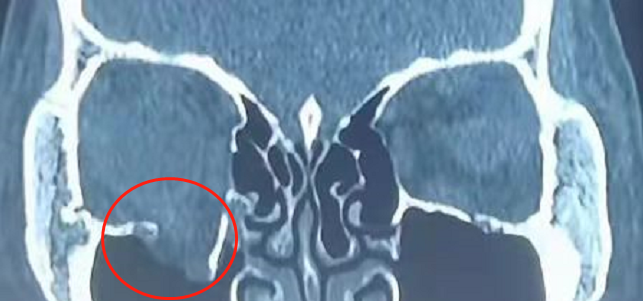

经眼眶 CT 检查后,李女士被诊断为「右侧眶下壁骨折」,医生建议保守治疗,因重影和眼球凹陷未改善,当地医生建议到福州爱尔眼科医院就诊。

日前,福州爱尔眼科医院泪道眼眶眼整形科主任刘健接诊了李女士。「患者眶骨骨折,还是需要尽快手术,否则会眼球塌陷直接影响面容,而且眼内肌肉嵌顿(卡住)及看东西重影的情况会一直存在。」排除手术禁忌后,刘健主任为李女士成功完成了右眼内镜下眶下壁骨折整复术。